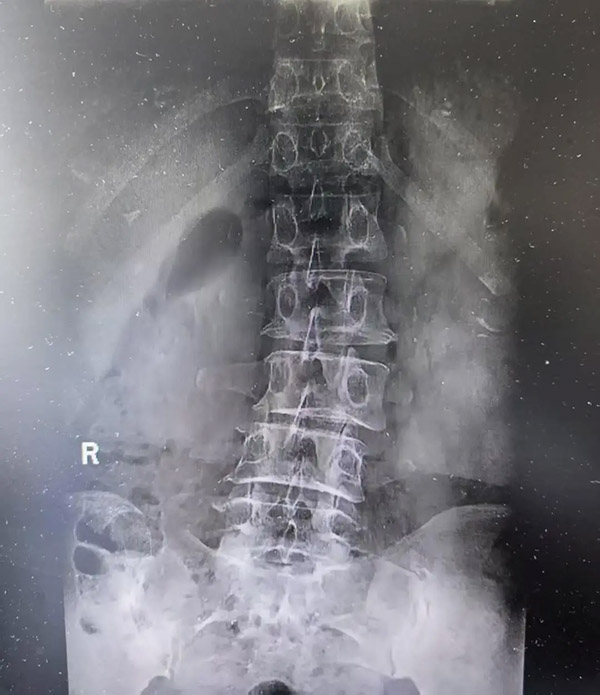

48岁的陶女士便是这项技术的受益者。两年前,她无明显诱因出现腰部剧烈疼痛。虽多次尝试理疗、药物等保守治疗,效果却始终不尽如人意。近3个月,陶女士的症状进一步恶化,疼痛放射至臀部及大腿,行走困难,严重影响日常生活。入院后,医生结合查体情况及影像学检查结果,明确诊断患者为腰4—5、腰5—骶1椎间盘突出症,伴有腰及左下肢持续性疼痛、间歇性跛行、腰部活动受限等典型表现。

考虑到患者担忧手术创伤大、术后恢复慢等问题,南院骨二科副主任高健带领团队经细致评估,为其量身制定了经皮腰椎间盘化学溶解术治疗方案。该术式无需开刀,仅在影像透视引导下,通过一根超细穿刺针精准抵达靶点并完成药物注射,利用专用药物溶解突出、脱出的髓核组织。手术全程患者意识清醒,无明显痛感,术后仅需卧床3小时即可下床活动,极大减轻了患者的身体创伤与心理负担。

据高健介绍,经皮腰椎间盘化学溶解术是国际公认的前沿超微创介入技术,核心优势为精准、微创、高效。手术采用0.7-1毫米的超细穿刺针,在DSA或CT实时引导下将胶原蛋白酶精准注入突出椎间盘部位,“智能识别”并特异性溶解髓核中的Ⅰ、Ⅱ型胶原纤维,使突出物回缩,从根源解除神经根压迫,缓解腰腿痛、麻木、行走受限等症状。相比传统开放手术,其创伤极小、针孔创口无需缝合,全程影像监控安全性高,术后当天即可下床活动,疗效稳定确切。同时,针对胶原酶常温易失活的问题,科室采用低温保存+现配现用方案以保障药物活性。此前接受治疗的患者术后疼痛评分均降至3分以下,肢体功能快速恢复,对微创治疗效果普遍给予高度认可。